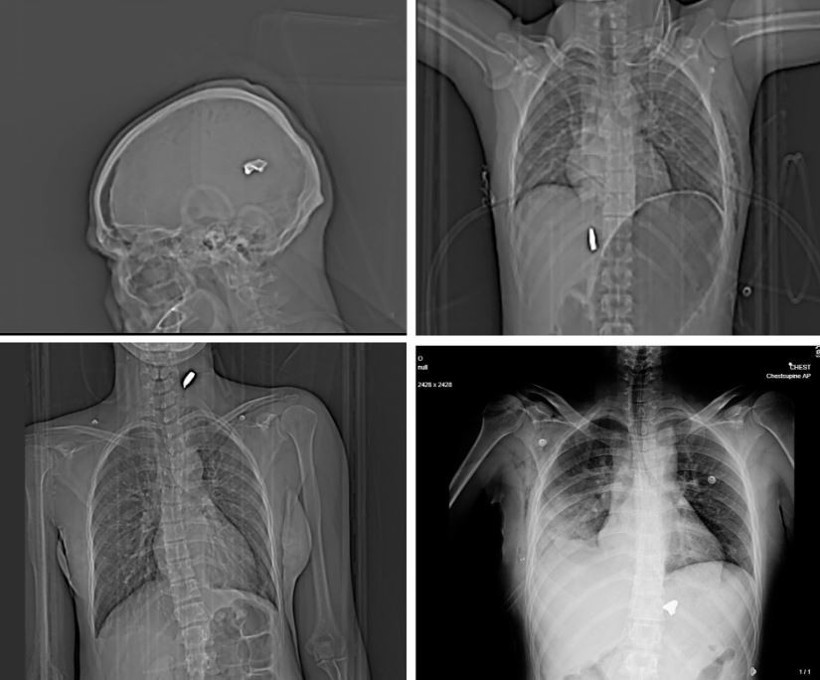

İngiliz gazetesi The Guardian ve şüpheli bilgilerin doğruluğunu teyit eden Factnameh'nin ortak araştırmasında ülkenin en büyük şehirlerinden birindeki tek bir hastaneden toplanan 75'ten fazla röntgen ve bilgisayarlı tomografi görüntüsü gözler önüne serildi.

Bu görüntüler, güvenlik güçlerinin yüksek kalibreli silahlar ve saçma kullandığı yönündeki iddiaları destekliyor. Röntgenlerin büyük bir kısmında protestoculara karşı "birdshot" olarak bilinen bir mühimmatın kullanıldığı ifade ediliyor.

Balistik uzmanları bazı görüntülerde vücuttaki mermilerin AK-47 ve KL-133 gibi taarruz tüfeklerinde kullanılan mermilere benzediğini belirtti.

Saldırıların daha çok yüz, göğüz ve genital bölgede yoğunlaşması da dikkat çekti. 2022'de patlak veren "Kadın, Yaşam, Özgürlük" protestolarında da benzer bir örüntü oluşmuştu.